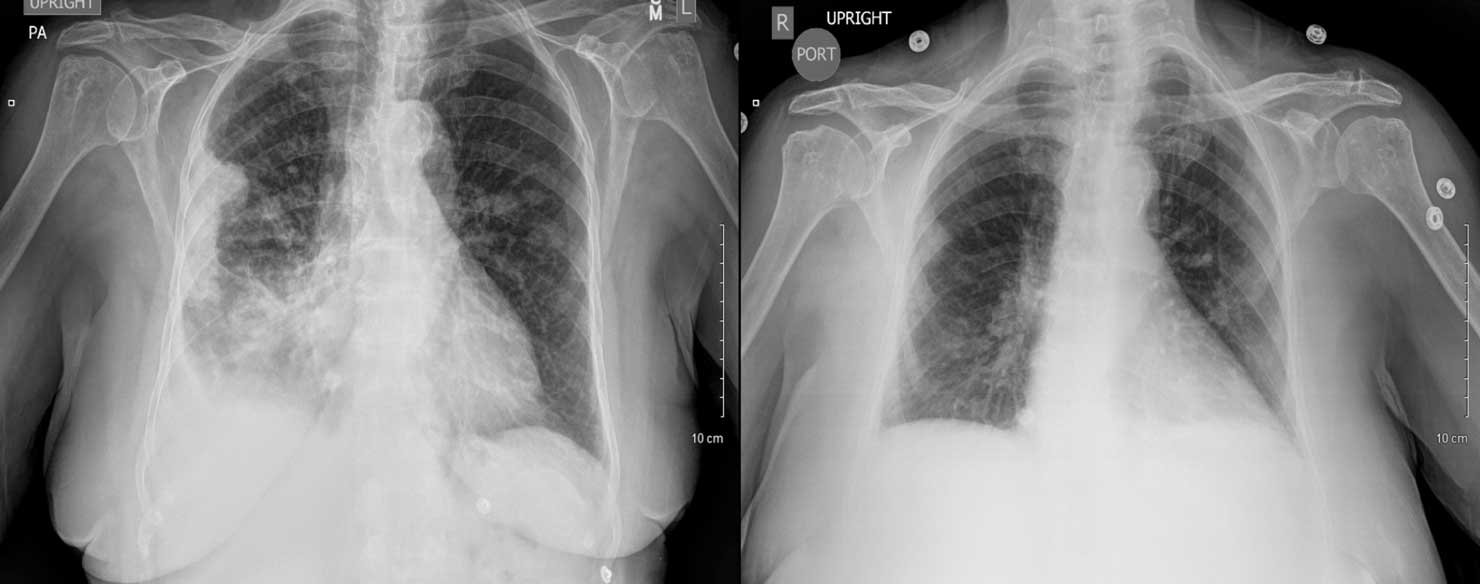

So, does mesothelioma show up on an X-ray? Not directly as "mesothelioma," but it can show abnormalities that are highly suspicious. Here are some common findings:

- Pleural Thickening: The lining of the lung can become noticeably thicker.

- Pleural Effusion: This is fluid buildup around the lungs, which can be a sign of irritation or disease.

- Pleural Plaques: These are areas of calcified scarring on the pleura, often a sign of past asbestos exposure.

- Volume Loss: One side of the chest might appear smaller due to lung constriction.

However, these signs are not exclusive to mesothelioma. Conditions like pneumonia, other cancers, or even heart failure can cause similar X-ray findings. This is why an X-ray is a screening tool, not a diagnostic one for mesothelioma.